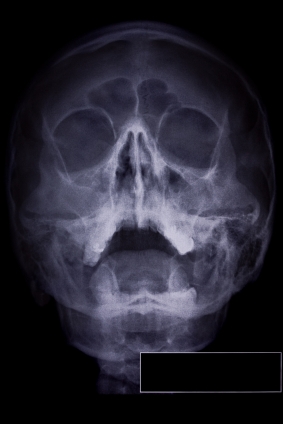

Гайморит это воспаление или инфекция придаточных пазух носа. Пазухи полости лицевой части черепа, и выстланы слизистой оболочкой. Гайморит это воспаление или инфекция этих пазух. Она развивается чаще всего в гайморовых пазух (под глазами) и решетчатой пазухи. В более серьезных инфекций инфекция может повлечь за собой кости (остеомиелита). Редко инфекция может распространиться на головной мозг и быть опасными для жизни.

ДИАГНОСТИКА

Изучение истории болезни и медицинский осмотр не проводятся. Порой КТ или МРТ будет сделано.